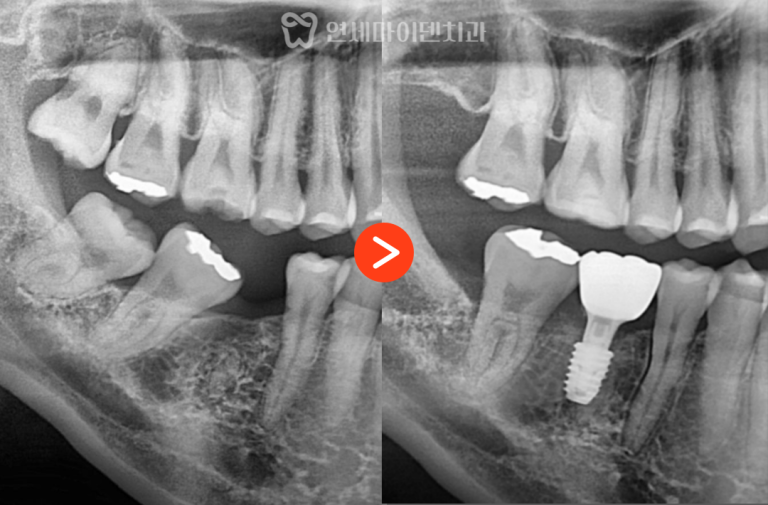

추가 엑스레이에서

치아 주변 뼈가 녹아 있는 소견이 나타났습니다.

초기 내원 당시에는 없던 변화였지만

불과 2~3주 사이에 급격하게 진행된 상태였습니다.

이 정도로 빠르게 뼈가 녹고

신경 괴사까지 동반된 경우라면

일반적으로는 발치를 고려하는 경우가 많습니다.

하지만 중요한 점은

이 변화가 ‘급성으로 진행된 염증’이라는 점이었습니다.

급성 염증으로 인한 뼈 소실은

원인을 제거하면

회복될 가능성이 상대적으로 높습니다.

시간이 지나면서

초기에 녹아 있던 뼈는

점차 다시 차오르는 양상이 확인되었습니다.

치료 1년 후에는

뼈가 거의 정상 수준으로 회복되었고,

약 4년이 지난 현재까지도

문제 없이 안정적으로 사용 중입니다.